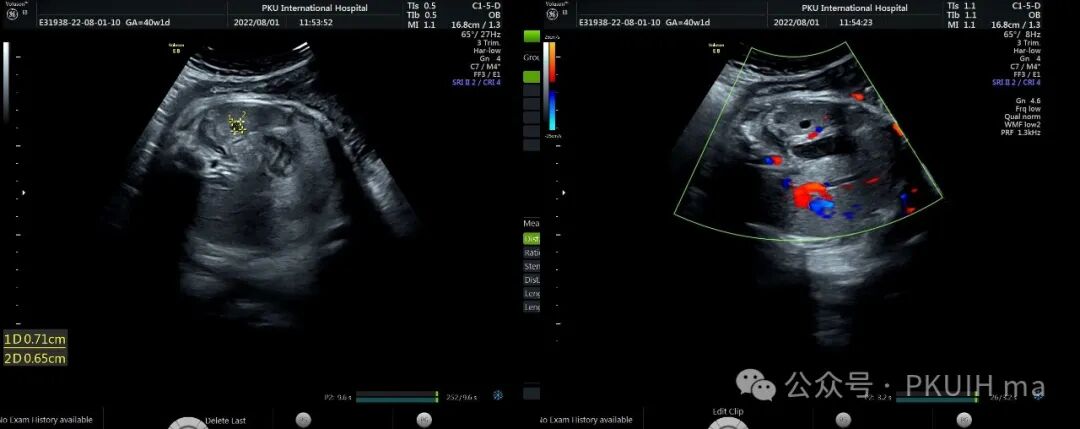

上两张图是一个孕36周发现的肝内单纯囊肿,出生后观察囊肿无变化。